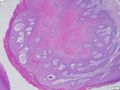

Non-malignant cystic

| Entity | Key histologic feature | Other features | Clinical | Stains/IHC | DDx | Other | Image |

|---|---|---|---|---|---|---|---|

| Epidermal cyst | cyst lined by squamous epithelium with a granular layer | keratinous debris, no skin adnexal structures | cyst | none | pilar cyst, dermoid cyst | Other? | |

| Pilar cyst (trichilemmal cyst) | cyst lined by squamous epithelium without a granular layer | keratinous debris | cyst | none | epidermal cyst | Other? | |